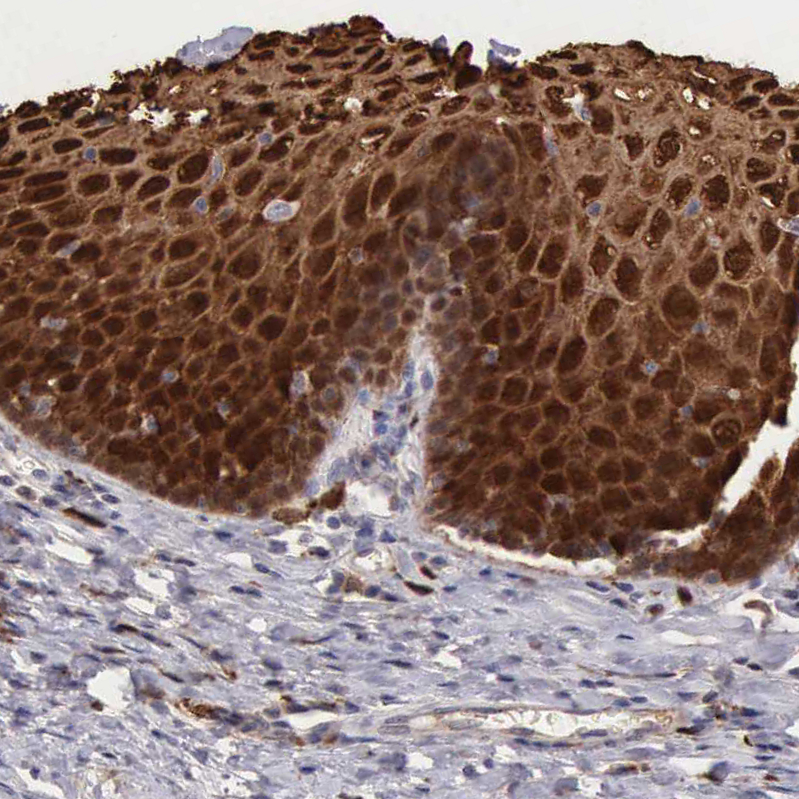

Immunohistochemical staining of human esophagus shows strong cytoplasmic and membranous positivity in squamous epithelial cells.